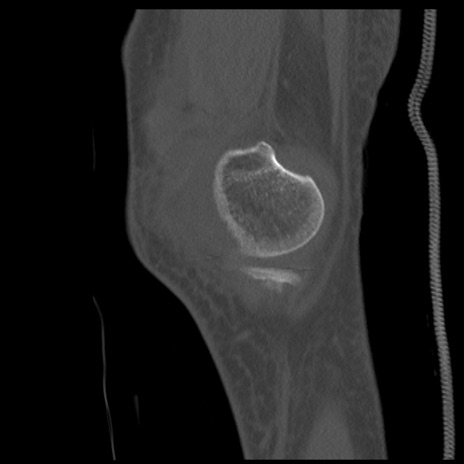

症例28 右膝関節CT(矢状断像)

右膝関節CT